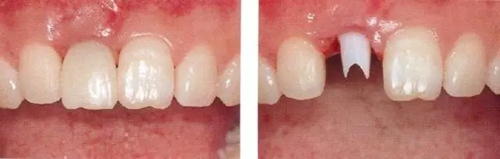

▲圖44-15,16

佩戴最終修復(fù)體時(shí)的正面口內(nèi)照和X光牙片。取得了很好的美觀狀態(tài)。

▲圖44-19,20

初診時(shí)和佩戴最終修復(fù)體時(shí)的狀態(tài)。適當(dāng)修正牙冠形態(tài)后,恢復(fù)了前牙的美觀性。